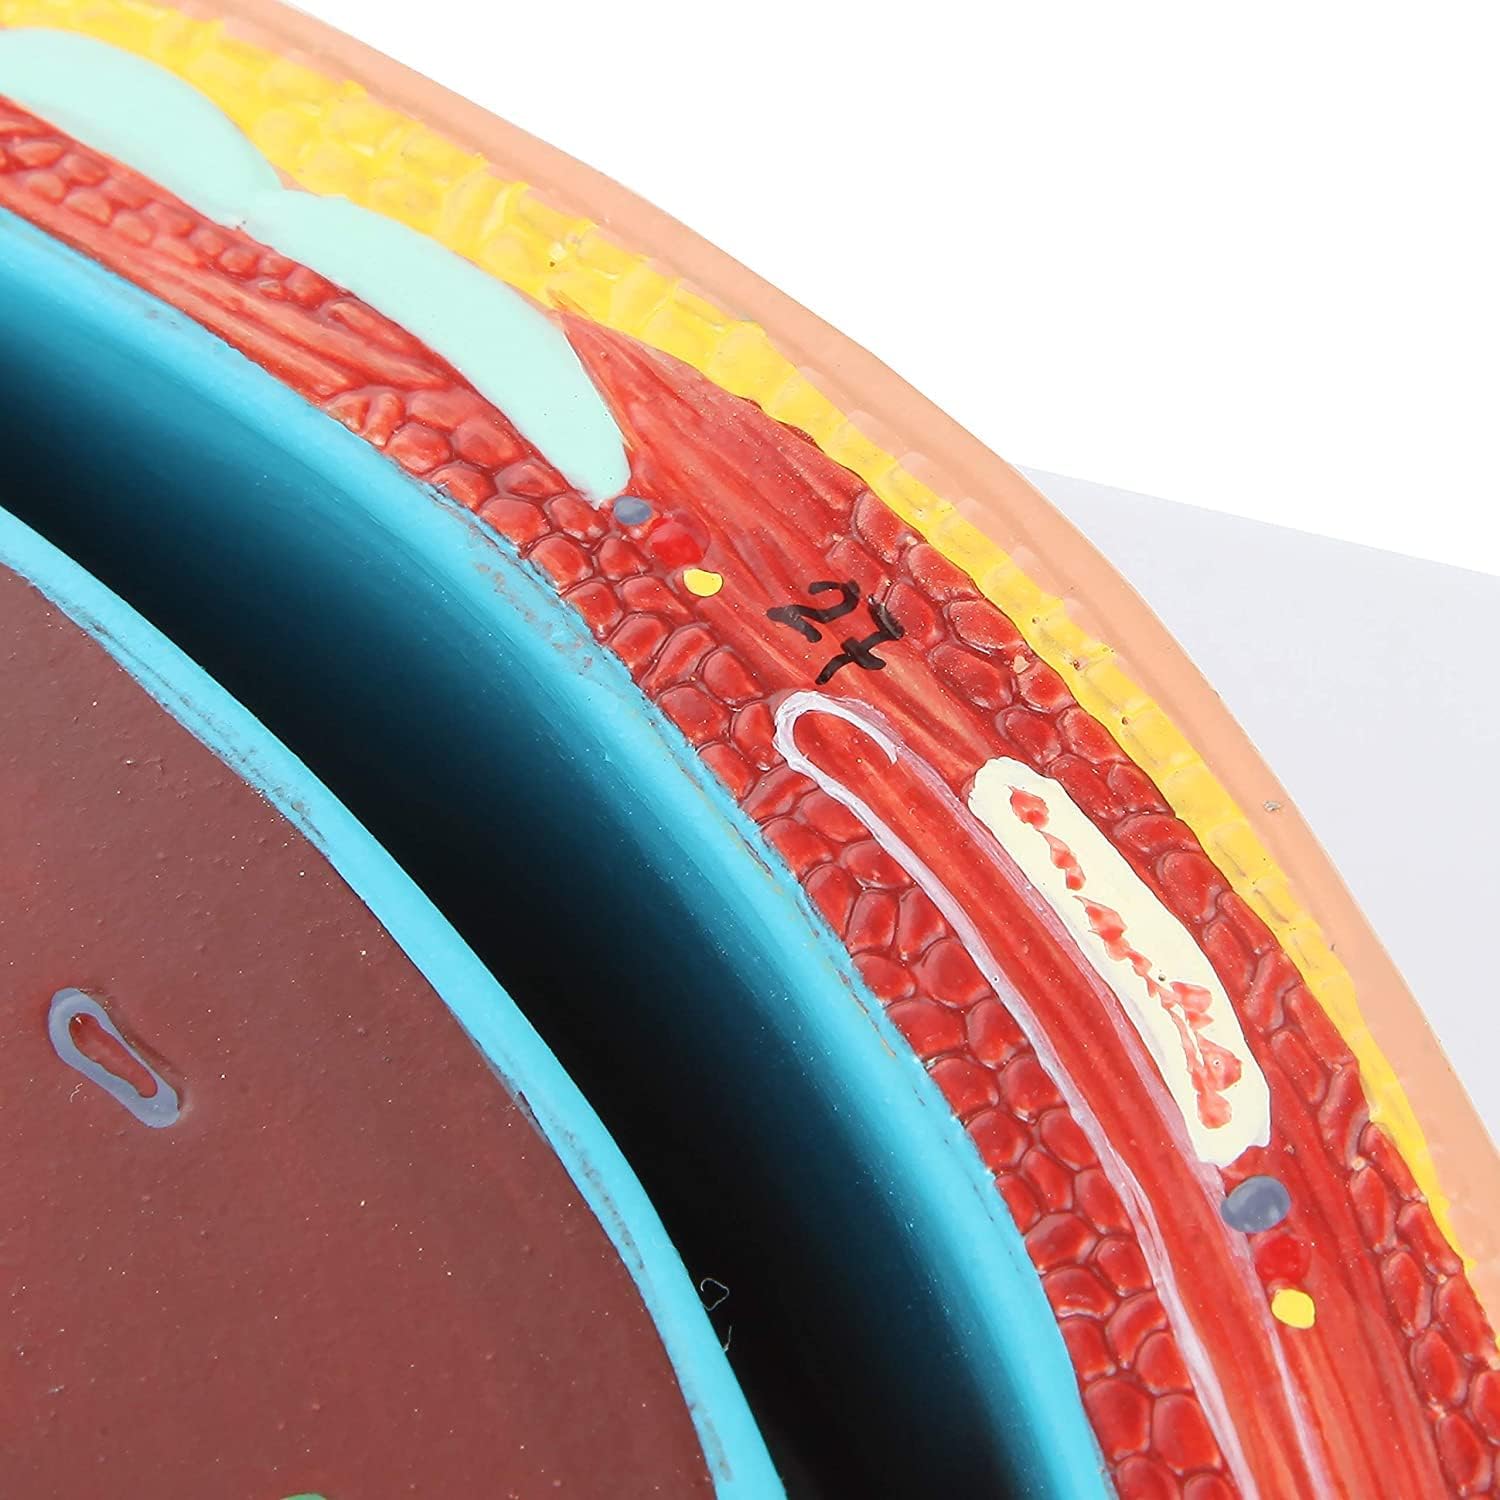

Hand Painted: made of food-grade PVC materials, computer color matching, high-grade hand-painted.

Anatomical Standard:According to the normal anatomical posture, the flat mediastinum is used as a cross-cut design, and the height of the eighth thoracic vertebra is shown in detail.